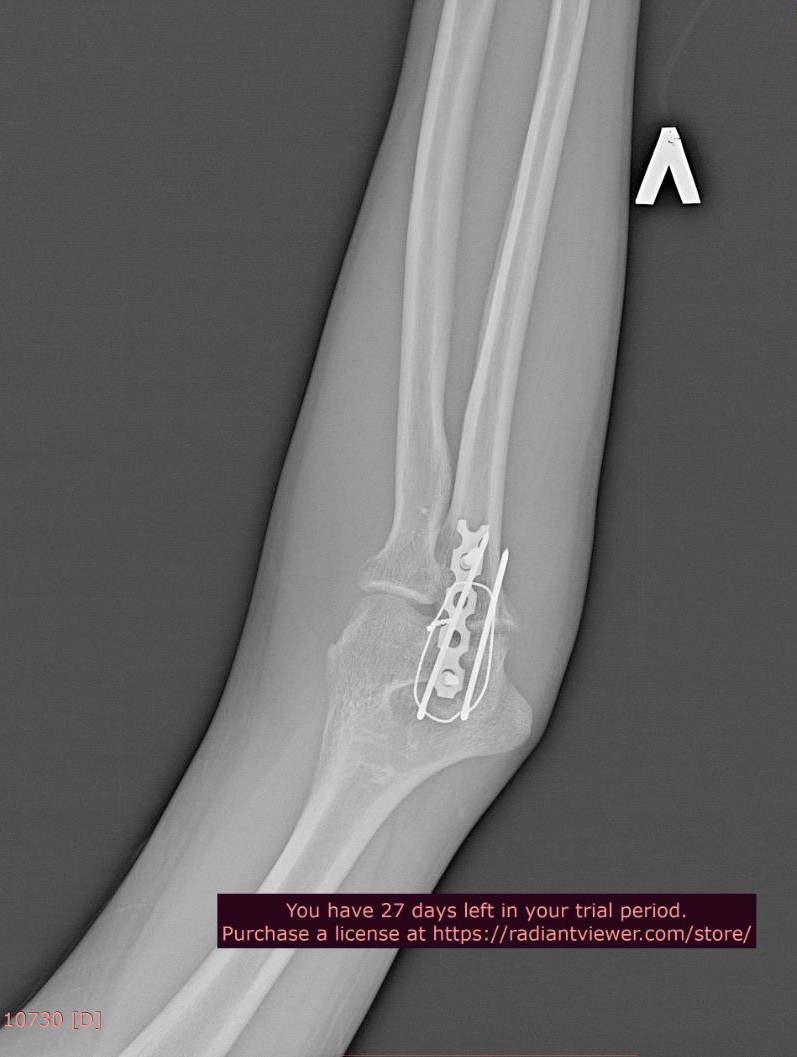

Добрый день. Два года назад упал с большой высоты, из-за чего мне установили металлоконструкции в плечевой и локтевой костях левой руки и в лучевой кости правой руки. Снимки ниже. Также имеются ограничения кисти на правой руке (из-за наличия пластины в лучевой кости), она разгибается максимум на 60 градусов из 90. Также, локтевая кость не разгибается до конца на пять градусов (что несущественно, но факт есть). Хотел бы уточнить, имею ли я возможность в моей ситуации получить категорию "В"? Спасибо.

Локтевая кость

Л2.jpg